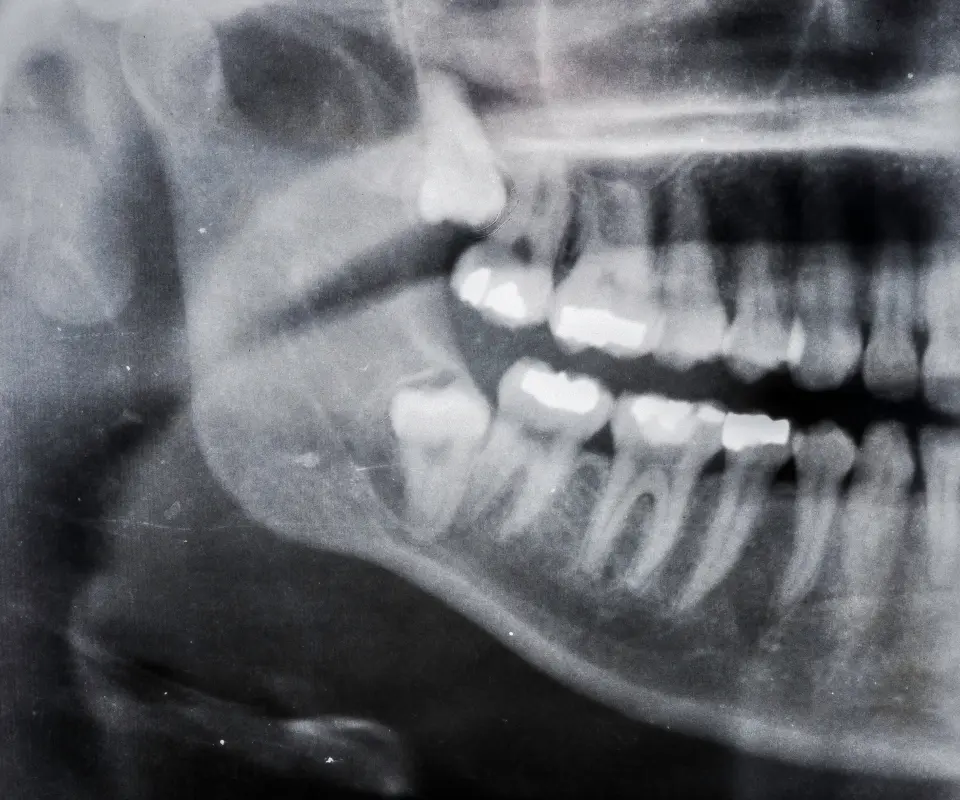

Tooth Abscess

A deep infection inside your tooth can cause severe pain, pus, and swelling in the jaw or face. This is often a dental emergency.

What is a dental abscess and how does it cause jaw swelling?

A dental abscess is a pocket of pus caused by a bacterial infection. It typically results from tooth decay, gum infections, or trauma. As the infection spreads, it can cause severe pain and visible jaw swelling. This condition needs urgent dental treatment to avoid further complications.